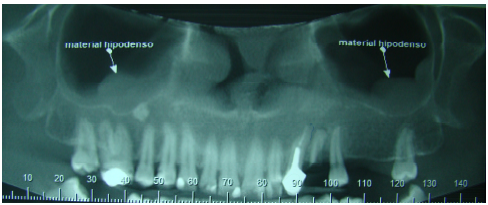

Observando a imagem abaixo e sabendo que não há sintomatologia relatada pelo paciente, marque a alternativa que corresponde ao diagnóstico radiográfico do material hipodenso:

Provas

Questão presente nas seguintes provas